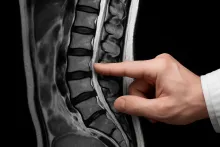

Если ваш врач подозревает конкретную причину болей в спине, он может направить вас на такие обследования, как рентген (хотя обычные рентгеновские снимки редко бывают полезны) или МРТ поясничного отдела позвоночника. МРТ сканирование визуализирует позвоночные диски, нервные корешки и мягкие ткани. МРТ, вероятно, является наиболее полезной техникой визуализации при боли в пояснице, поскольку оно может показать проблемы с дисками и когда что-то давит на нервы спинного мозга. Иногда предлагается компьютерная томография, если МРТ недоступно.